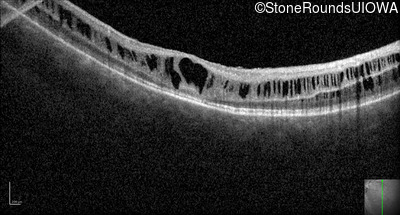

Optical Coherence Tomography - Right - 10/40

Exemplar / OCT Stack